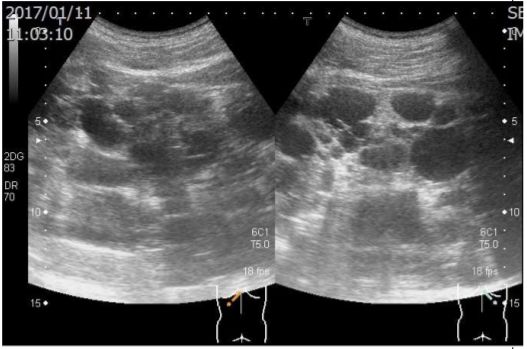

12. 某45歲男性已有高血壓5年,最近檢查有血尿RBC 10-20/HPF、Cre 1.2 mg/dL、超音波檢查發現兩側腎臟長徑超過15公分(如圖)及各有囊腫數目超過十個;家族史為父親自60歲開始血液透析,不曾顱內出血,父親的腎臟超音波亦有雷同的發現。 請問關於其腎臟疾病之敘述,下列何者為正確?(1)每年定期追蹤腎功能,即為預估日後是否需要透析治療之最敏感方法;(2)若其太太懷孕可做產前篩檢,其子女遺傳此腎臟疾病的機會為50%;(3) 以影像學檢查估算其腎臟體積,若超過600立方公分,其腎功能極可能持續逐年惡化;(4) 雖無症狀,應每年安排腦部血管Magnetic resonance angiography的檢查;(5)宜建議停止服用含女性荷爾蒙之避孕藥。 (A) (1)+(2)+(3) (B) (1)+(3)+(4) (C) (2)+(4) (D) (4)+(5) (E) (2)+(3)+(5)